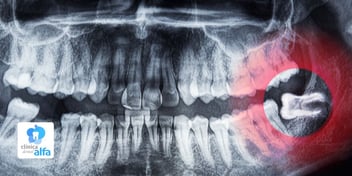

Restablecen tanto la función masticatoria como la estética. - Implantes dentales

Son la solución ideal cuando se ha perdido una o más piezas dentales. Consisten en un tornillo de titanio que se integra al hueso maxilar y posteriormente se cubre con una corona.

Este tratamiento combina cirugía y rehabilitación, ofreciendo una solución permanente, funcional y natural. - Prótesis dentales